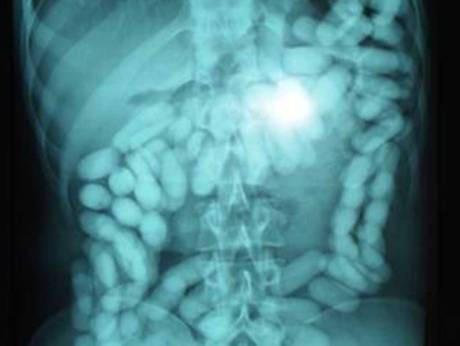

இதனால் மீதம் எவ்வளவு உள்ளது என்பதைப் பார்ப்பதற்காக மருத்துவர்கள் வயிற்றுப்பகுதியை பரிசோதனை செய்து பார்த்ததில் அதிர்ச்சியடைந்துள்ளனர். காரணம் அவருடைய வயிற்றில் இன்னும் 98 போதைமருந்துகள் உள்ளதாக மருத்துவர்கள் பொலிசாருக்கு தெரிவித்துள்ளனர்.

அதன் மொத்த எடை 1.36kg என்றும் இதன் மதிப்பு Dh500,000 (இலங்கை மதிப்பு (20,15,86,13 கோடி) வரை இருக்கும் என கூறப்படுகிறது.